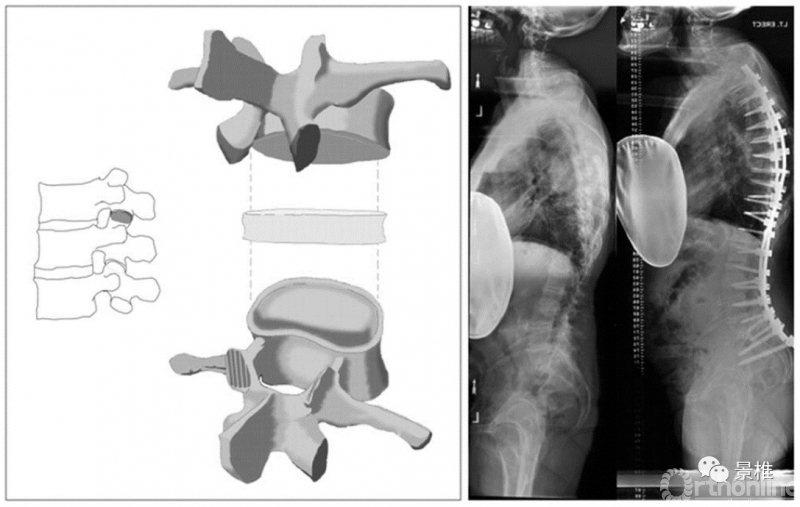

1级 SPO

1级,关节突部分截除,也就是常说的SPO(Smith-Petersen osteotomy),发明于1945年。最初用在腰椎。后凸矫形约10º。

SPO简明图解:

SPO(Smith-Peterson)截骨,也叫后柱截骨PCO,或者Ponte截骨。顾名思义,截除椎体后方部分棘突、椎板、关节突,保留了椎弓根结构。

截除1mm后柱结构,可以获得1°矫正,一般单节段PCO可以纠正10°的后凸。